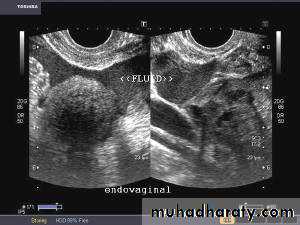

Hemorrhagic cyst of ovary with ruptured ectopic pregnancy:This female patient has a left ovarian hemorrhagic cyst (see ultrasound image above-left). In addition, there is a large collection of free fluid with particulate matter in the pelvis. The right fallopian tube is thickened with a ring shaped mass. This suggests that there is significant hemorrhage into the pelvis due to a ruptured ectopic pregnancy (right tubal ectopic gestation). The left ovarian hemorrhagic cyst appears intact, ruling out ruptured hemorrhagic cyst.